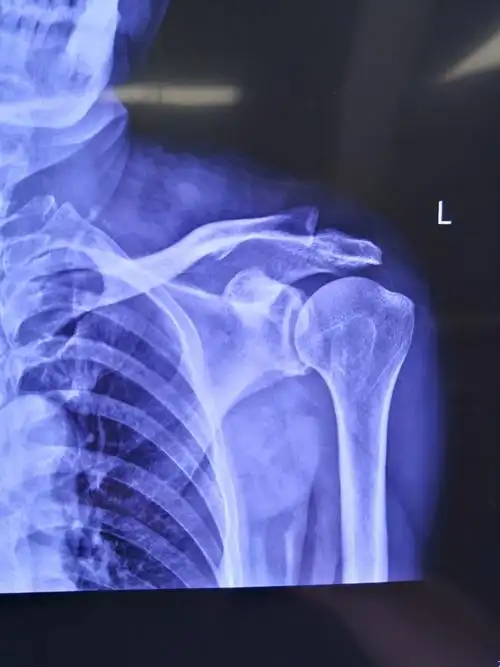

肩肱骨骨折,有x光片,请医生咨询

术前左肩关节正位片提示:左肱骨大结节处骨赘形成(肩峰撞击引起)

肩关节半脱位